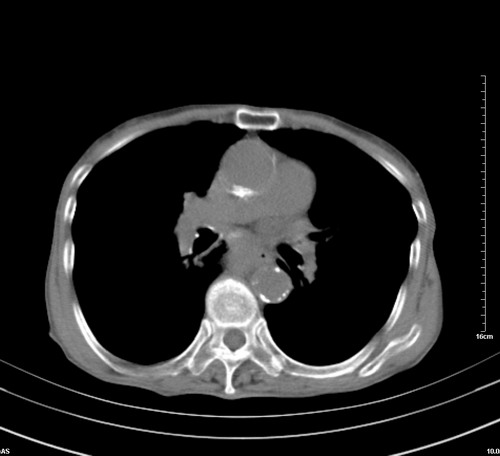

中后纵隔占位,气管、食道受压、变形、移位。恶性可能性大。

考虑:中后纵隔转移瘤可能性大,主动脉硬化。

中后纵隔占位, 考虑:转移瘤不除外.

纵隔淋巴结肿大,考虑转移而来

肺癌,纵隔淋巴结转移,肝左叶病变考虑为转移病灶。

后中纵隔团块影,伴气管、食道受压移位,首先考虑转移瘤,肝s5段低密度灶。建议增强检查,另外其结肠是否有问题请提供,右肺部分肺叶局限含气增多,考虑局限肺气肿。

建议强化检查,考虑纵隔型肺癌,小细胞可能性大。

后中纵隔团块影,伴气管、食道受压移位,首先考虑转移瘤,肝表现同11773。

后中纵隔淋巴结肿大,首先考虑转移瘤。